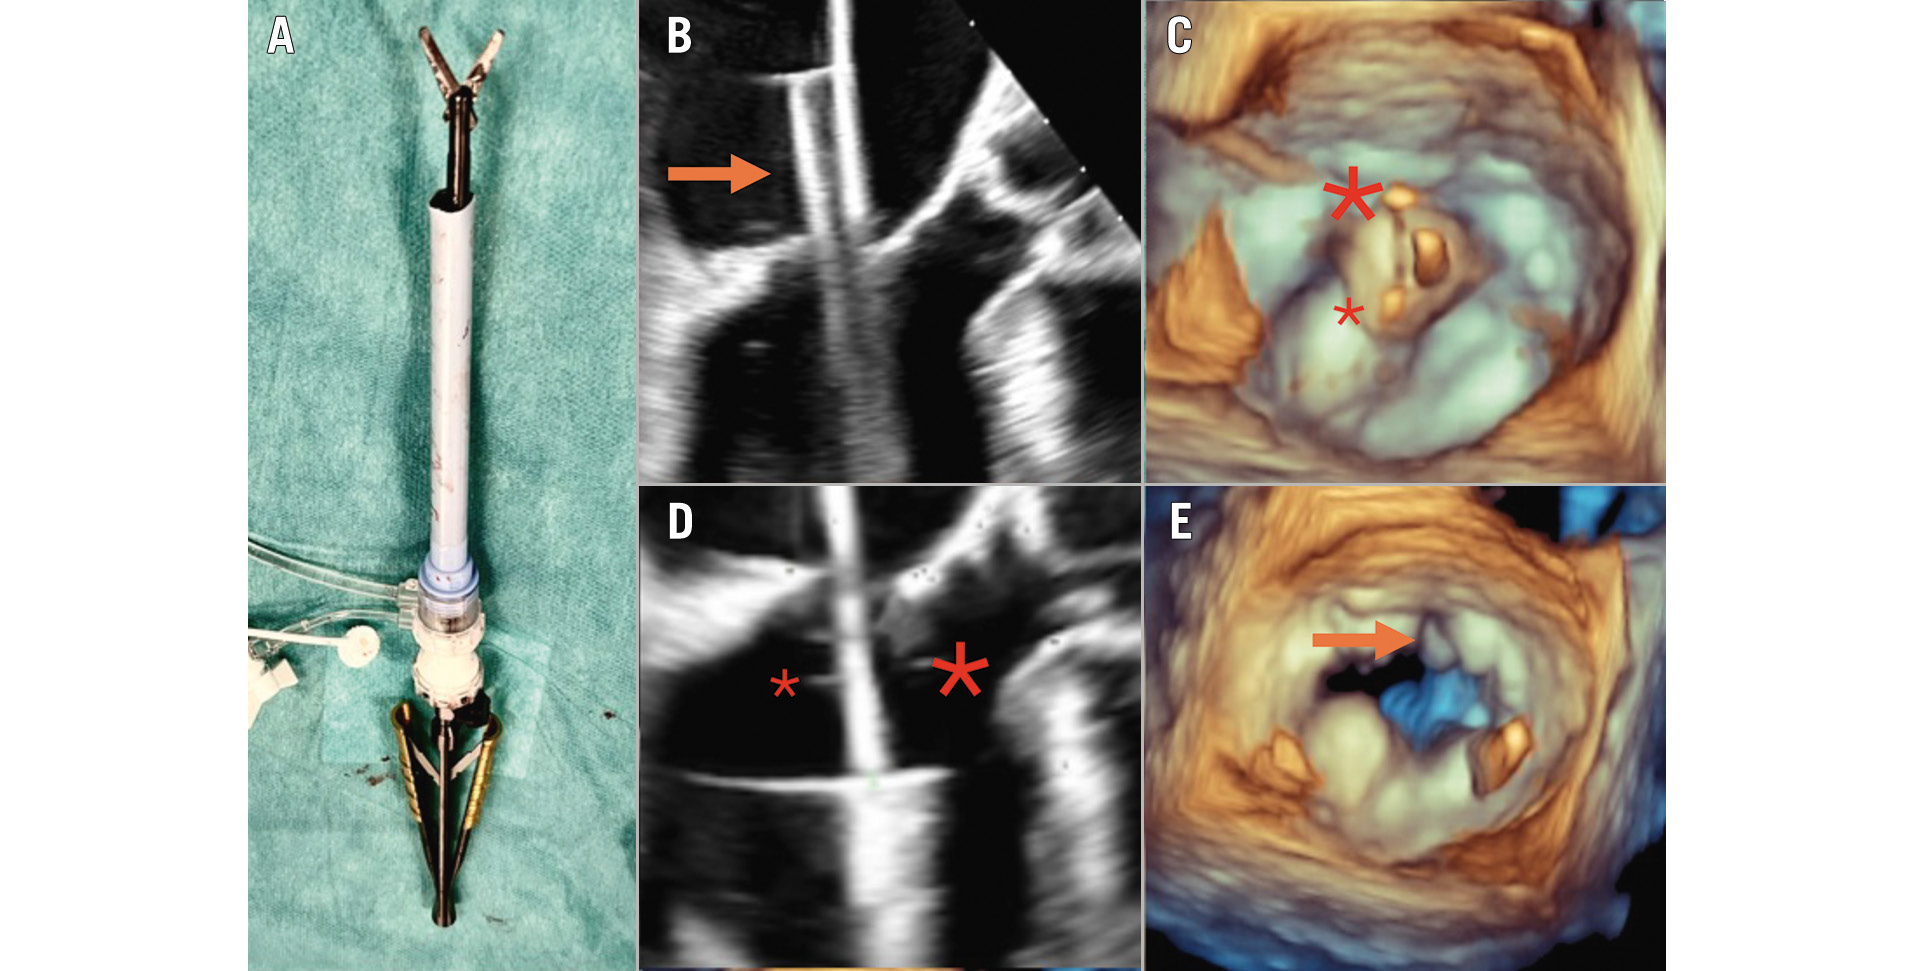

The Heart Team elected to perform the MitraCut procedure in patients with a small predicted LVOT (but above the cutoff for Tendyne implantation), in patients with a long anterior mitral valve leaflet or if a potential risk for fixed or dynamic LVOT obstruction based on preoperative or intraoperative imaging was perceived (Supplementary Table 1). The MitraCut procedure was performed using endoscopic shafted scissors and a manually shortened large-bore sheath (Moving image 1). The diameter and the length of the sheath were chosen based on the size and length of the endoscopic scissors’ shaft; the sheath was typically shortened to a length of between 10 and 15 cm. After carefully flushing the shortened sheath, the endoscopic scissors were introduced inside the sheath to check the length (Figure 1A).

After performing a standard apical access, heparinisation, and “flossing” manoeuvre to exclude any entanglement of the guidewire in the subvalvular apparatus20, the modified sheath and its indwelling dilator were passed through the apical myocardium into the left ventricle while maintaining the guidewire tip’s position in the pulmonary vein. This dilator was later replaced by the scissors through the sheath. The sheath was advanced into the left atrium to approximately 2 cm above the MV plane (Figure 1B). The tip of the scissors was pushed out of the sheath and opened to demonstrate appropriate alignment under three-dimensional (3D) echocardiography (Figure 1C). Once correct alignment in the centre of the MV was achieved, the open scissors and the sheath were simultaneously retracted into the left ventricle. Guided by an X-plane view of the left ventricle (intercommissural view, LVOT view), the AML was trapped between the scissor blades and sharply transected in the A2 segment (Central illustration, Figure 1D). The effectiveness of the transection was assessed based on a 3D en-face view of the MV (Figure 1E). After the cuts were complete, the scissors were retracted into the sheath, facilitating their removal without risk of tissue damage. The MitraCut procedure was followed by TMVR with the Tendyne valve system, as previously described in detail520.

Figure 1. The MitraCut procedure. Illustration of the off-table preparation after manual shortening of the large-bore sheath and insertion of the endoscopic scissors (A). The sheath and the covered scissors (orange arrow) are inserted up to approximately 2 cm above the MV plane (B), followed by alignment of the scissors (C; big asterisk above the AML, small asterisk above the posterior leaflet). The scissors together with the sheath are carefully retracted into the left ventricle, enabling the grasping of the AML (D). The post-MitraCut three-dimensional en-face view demonstrates successful AML division (E). Adapted and changed from Andreas et al16. AML: anterior mitral leaflet; MV: mitral valve